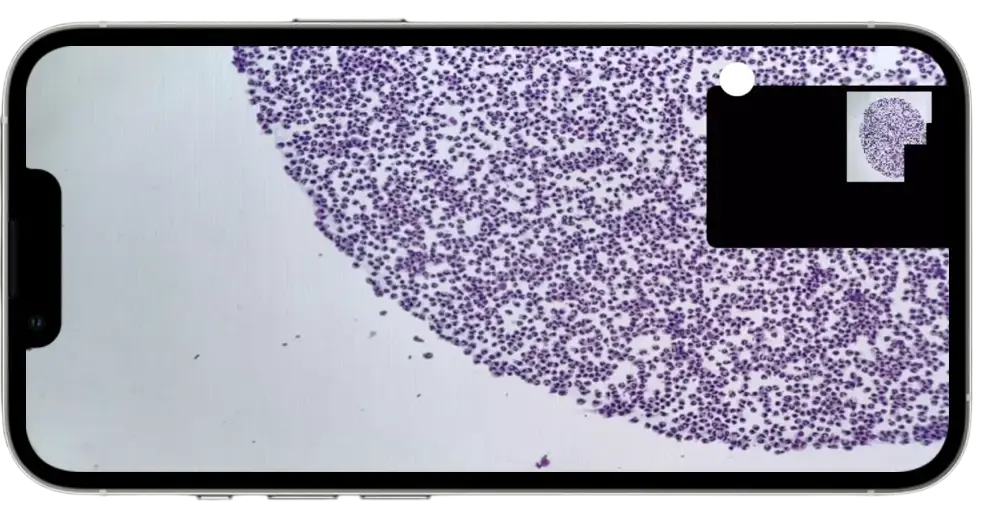

Celly's innovative iPhone-based solution converts your existing microscope into a powerful digital diagnostic platform, with real-time AI analysis that revolutionizes your workflow.

Transform Your Microscope into a Digital Pathology Platform

Instantly convert your existing microscope into a powerful digital scanner without investing in expensive specialized equipment.

Create high-resolution digital slide images that are securely stored in the cloud, enabling seamless telepathology consultations, remote diagnoses, and advanced educational opportunities.

Transform your laboratory workflow with our motorized stage for microscope. Hands-free slide scanning and batch processing of up to 10 slides.

Seamlessly integrates with your existing microscope setup, eliminating the need for expensive dedicated slide scanners.